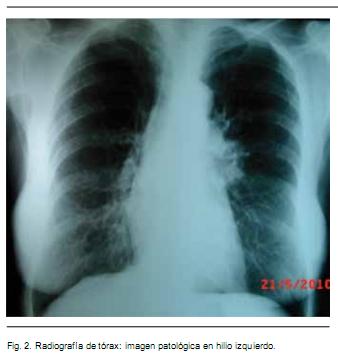

El examen linfoganglionar muestra adenopatías carotídeas bilaterales, medianas, fibroelásticas, indoloras y una adenopatía supraclavicular izquierda de 2 cm, pétrea e indolora, siendo el resto del examen normal. En la radiografía de tórax se destaca una imagen patológica a nivel de hilio izquierdo (Figura 2). La tomografía computada tóraco-abdómino-pélvica confirma el proceso patológico en el hilio izquierdo y revela micronódulo subpleural en lóbulo superior izquierdo y otro de 6 mm paramediastinal en lóbulo superior derecho, así como adenomegalias mediastinales a nivel de ventana aortopulmonar, laterotraqueales derechas, subcarinales e hiliares izquierdas. La paraclínica humoral mostró VES: 92 mm; PCR: 96; ANA: reactivo 1/160 patrón nuclear homogéneo; ANCA: no reactivo, FR: negativo, serologías para VIH, VHB, VHC: negativas. Glicemia: 97 mg%; Hemograma: GB: 7.7OO/mm3, Hb. 12,3 g/dl, Plq.: 400.000/mm3.

El caso 1 se trata de una paciente cuyo motivo de ingreso está determinado por el dolor originado en las lesiones vasculíticas de los dedos de ambas manos con pequeñas áreas de necrosis a nivel de los pulpejos. Los hallazgos clínicos y paraclínicos demuestran que la paciente era portadora de una enfermedad neoplásica de origen broncopulmonar como lo atestigua la presencia radiológica y tomográfica de una imagen tumoral a nivel del hilio izquierdo. Se trata de un estadio avanzado (estadío IV) dada la presencia de adenopatías supraclaviculares de estirpe neoplásica y de histopatología correspondiente a un carcinoma epidermoide.